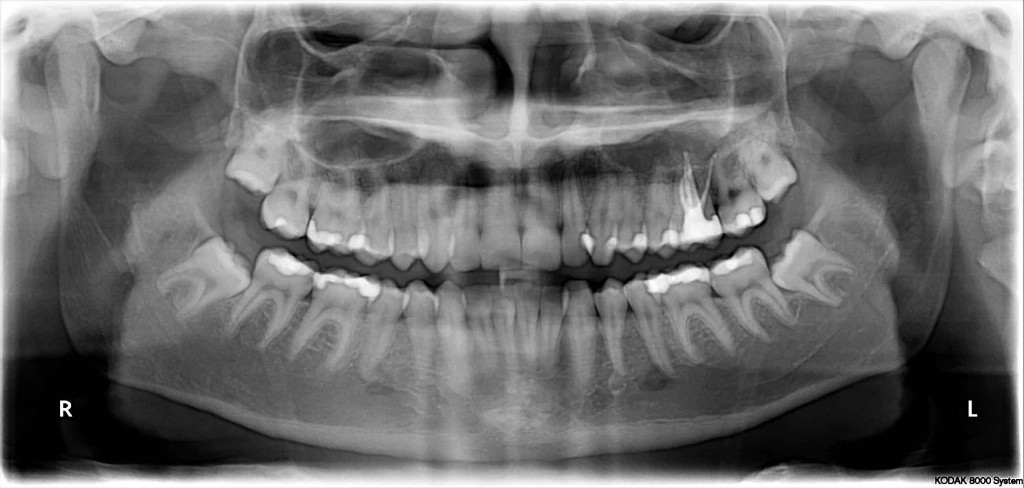

melkgebit gebit blijvende nummering tandheelkunde